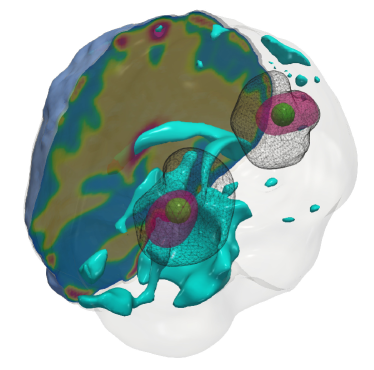

Fig. 4: (a) Description of the visualized brain sub-structures: The figure on the left shows an isometric view of the brain with different tumorous and healthy tissue sub-structures. The figure on the right zooms in on the tumor region and describes each structure. (b, c) Qualitative results for the artificial tumor test-case AT-C1 (a mono-focal, mostly proliferative tumor) with growth parameters ρ=8,κ=0.025formulae-sequencesuperscript𝜌8superscript𝜅0.025\rho^{\star}=8,~{}\kappa^{\star}=0.025. The images show the tumor data (gray wireframe), ground truth tumor initial condition (green volume), reconstructed tumor initial condition (magenta volume), ventricles (cyan volume), and a section of the patient brain geometry. We observe exact reconstruction for smaller tumors with sparsity constraints. The \mathboldL2\mathboldsubscript𝐿2\mathbold{L_{2}} solver fails to obtain the same reconstruction due to its inability to determine the correct reaction coefficient. We refer the reader to Tab. 4 for the quality of final tumor reconstruction.

(a)

Refer to caption

(b) \mathboldL2\mathboldsubscript𝐿2\mathbold{L_{2}}

(c) CS